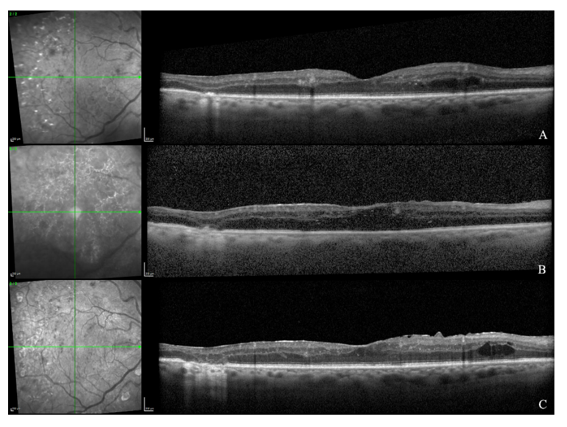

Visual acuity (VA) was 20/30 in the OD and 20/20 in the OS. At baseline, optical coherence tomography (OCT) of both eyes demonstrated disorganization of the retinal inner layers (DRIL) with scattered intraretinal cystoid spaces (Figure 1A).

Figure 1 OCT of the OD at baseline (A), five days after PPV (B), and at the last follow-up (C).

(A) Baseline shows DRIL with intraretinal cysts

(B) Early postoperative imaging reveals media-related signal attenuation with preserved foveal architecture and a mild ERM

(C) Final follow-up demonstrates an ERM with foveal contour distortion, persistent DRIL, and rare residual cysts.

On the first postoperative day following PPV, VA in the OD was CF. Slit-lamp examination revealed a 2 mm hypopyon, a clear pupillary center, and residual fine rubeosis iridis; (Figure 2). Five days after PPV, OCT of the OD demonstrated diffuse signal attenuation due to postoperative media opacity, with overall preservation of the foveal architecture and outer retinal bands, and a mild epiretinal membrane (ERM) (Figure 1B).

At eighteen months, VA was 20/30 in the OD and 20/25 in the OS. IOP was stable at 13 mmHg and 15 mmHg, respectively. Both corneas were clear, with no evidence of rubeosis. Mild anterior capsule fibrosis was noted in the OD, but the IOL remained well centered and stable. At the last follow-up, OCT of the OD revealed an ERM with mild foveal contour distortion, persistent DRIL, and rare residual intraretinal cysts (Figure 1C).